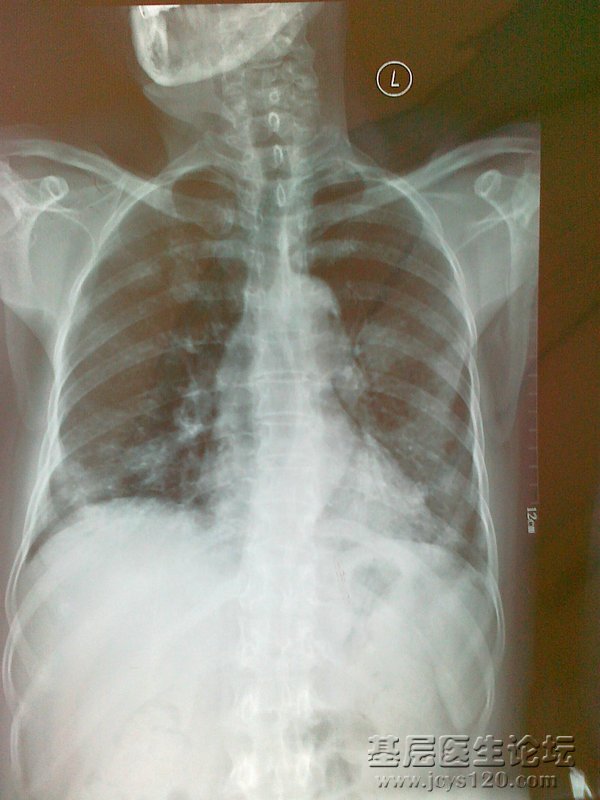

患者,女,67岁,因低热、咳嗽一个月来诊,患者一个月前无明显诱因出现发热、咳嗽,体温在37.5-37.8°c 无寒战、盗汗、乏力。偶有咳白色粘液痰,无胸痛、胸闷,无活动后气喘,在当地门诊输液“青霉素”治疗8天效果不好,发病来饮食,睡眠可,大小便正常,体重无明显变化。

查体:全身浅表淋巴结未触及肿大,双肺叩诊清音,呼吸音粗,未闻及明显干湿啰音,心脏听诊未见明显异常。

胸部CT:双肺多个团块影。 血常规:WBC:13.3×10 9/L 中性粒细胞比率:70.5% HGB:122g/L PLT:259×10 9/L 。